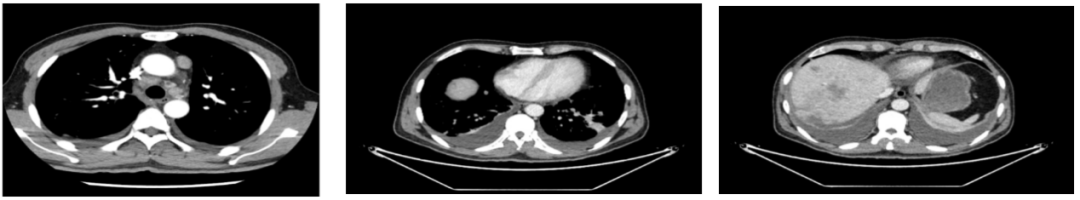

2020年4月复查:持续PR

肿瘤标志物:均正常

肝功能正常。

增强CT示:肝硬化

肝异常强化灶

考虑酒精性肝硬化可能性大,未基线使用替吉奥维持治疗。